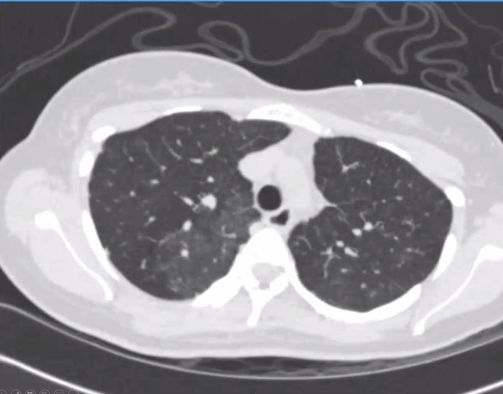

Lots of mosaic attenuation!

She goes to the ED and gets another CT... mosaicism is still there but now she has a new bilateral pleural effusions and interlobular septal thickening and atelectasis.

Whoops - seem to have accidentally started a new thread for the rest of the case. Case continues with the remainder of the HPI in image below, followed by CT scan here: